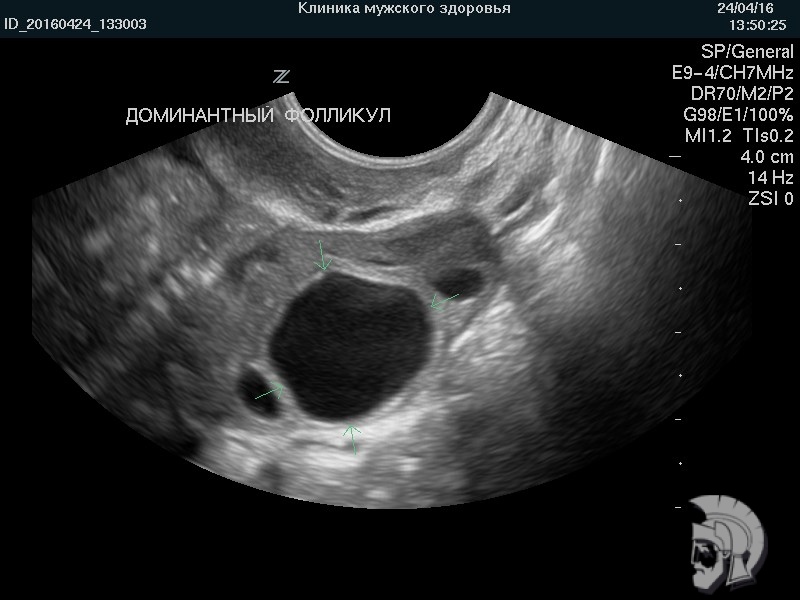

| Фото фолликулометрии. Наиболее крупный фолликул (доминантный фолликул) указан стрелками |

| Фото фолликулометрии. Созревший (преовуляторный) фолликул в яичнике указан стрелками |